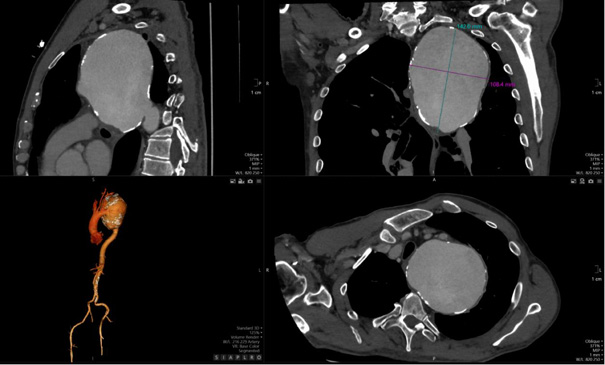

The detection of a mediastinal mass prompted differential diagnostic considerations, primarily focusing on two major possibilities: (1) mediastinal tumor formation associated with lymphocytic infiltration due to leukemia or other oncological masses, and (2) a giant vascular aneurysm. To delineate the etiology, a two-dimensional CT scan of the thoracic aorta was performed, as shown in Figure 2, revealing a large aneurysm in the distal post-arch segment of the descending aorta. The observed mass corresponds to a giant aneurysmal dilation.

The aneurysm measured 14.08 × 10.04 cm in its maximum transverse diameters. No chronic thrombus was identified within the tunica media, nor was there any evidence of dissection. The proximal ascending aorta measured 38 mm in diameter. Figure 3, which depicts a three-dimensional CT reconstruction, delineates the anatomical relationship of the aneurysm with the aortic arch, the left subclavian artery, and the descending thoracic aorta. The aneurysm was localized, with no involvement of the proximal left subclavian artery or its orifice. The distal portion of the aneurysm did not extend to spinal or intercostal branches. The remainder of the aorta, including the abdominal segment, appeared normal. The primary clinical impact of the aneurysm was attributed to a significant mass effect, leading to compression of the trachea and bronchi as well as potential irritation of the left phrenic nerve secondary to mediastinal compression.

CT angiography remains the gold standard for the diagnosis and assessment of the extent of GDTAA [21]. It allows high-resolution visualisation of the size and morphology of the aneurysm as well as the anatomical relationships with the adjacent structures [21]. In this case, CT imaging confirmed a massive aneurysm with significant displacement of the trachea and compression of the bronchi, thereby emphasising the crucial role of modern imaging in surgical planning [21].

Surgical intervention is the primary method of treating GDTAA, especially if the aneurysm is larger than 6.5 cm or symptomatic [22]. Open surgical repair, as performed in this case, involves resection of the aneurysmal segment and replacement with a Dacron graft, which has been shown to be durable over time [23]. Thoracic Endovascular Aortic Repair (TEVAR) is a new alternative that is associated with less perioperative morbidity and faster recovery [3]. However, its applicability is limited in cases of an extreme aneurysm size or unfavourable anatomical configurations [24].

In the presented case, open surgical repair was chosen due to the giant size of the aneurysm and its anatomical complexity, which would have posed significant challenges for endovascular stent placement [24]. The simultaneous performance of Coronary Artery Bypass Grafting (CABG) is another example of the need to consider concomitant cardiovascular conditions when repairing an aortic aneurysm [25].